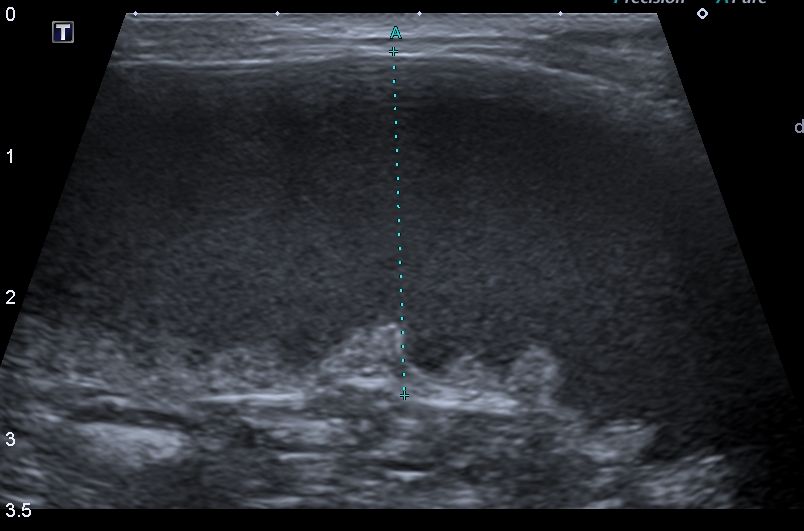

담담하게 확장되어 있는 자궁

몸집이 작으면서도 팽창하는 듯한 배